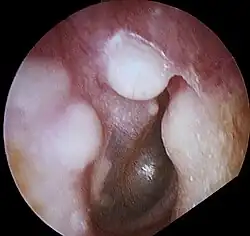

Osteoma of external auditory meatus